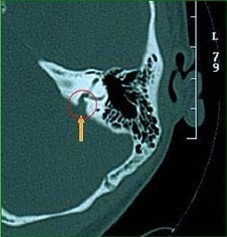

感觉声音的主要结构—内耳是由骨迷路和膜迷路组成,膜迷路内有内淋巴液,内淋巴液的正常代谢对维持正常的听力是至关重要的。前庭导水管将膜迷路与内淋巴囊相连,而正常大小的导水管是维持内淋巴液代谢所必需的。由于先天发育异常导致前庭导水管扩大时,内淋巴液可经过扩大的前庭导水管从内淋巴囊倒流于耳蜗或前庭,损伤感觉毛细胞出现聋或眩晕。在耳部CT或MRI影像检查中存在前庭导水管扩大症者占1%;患儿一般情况下出生时听力一般接近正常,躲在3-4岁时发病;感冒和外伤也常常是发病的诱因,及时轻微的外伤也可以引起重度感音神经性聋和眩晕。采用神经营养剂治疗,有一定效果,部分患儿的听力可恢复到原有水平,但仍较正常儿童厅里查,听力容易波动,目前尚无特效的治疗方法。

附前庭CT图、